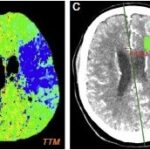

Los estudios de TC permiten evidenciar los accidentes cerebrovasculares (ACV) ocasionados por el abuso de la cocaína. Por caso, se localizó en la literatura imágenes que permiten ver el ACV isquémico agudo de la arteria cerebral media izquierda de un paciente. La TC sin contraste intravenoso visualiza la hipodensidad de la cabeza del caudado, del núcleo lenticular y de la ínsula izquierda. También se realizaron estudios de RM, que permiten observar la restricción del área isquémica en el territorio silviano(18) (ver Imagen 5).

Los consumidores habituales de cocaína suelen tener un pico de presión arterial sistólica elevada y un aumento de la frecuencia cardíaca tras el consumo, que los hace propensos a sufrir malformaciones arterovenosas. Al mismo tiempo, si esta sustancia se combina con etanol, las probabilidad de padecer una hemorragia subaracnoidea se incrementan. A propósito, se puede mencionar el caso de una paciente de 33 años de edad con síntomas de cefalea intensa y hemiparesia izquierda, en cuyo análisis de tóxicos de orina se detectó cocaína.(18)

En el caso que se viene reseñando, se realizó TC sin contraste para evidenciar eventuales daños isquémicos. En este estudio se localizó un hematoma intraparenquimatoso (ver Imagen 6). Este tipo de hematomas tiene un significativo riesgo para la persona, dado que puede avanzar hacia hemorragias con daño en la barrera hematoencefálica e incremento de la presión intracraneal, que puede ocasionar déficit neurológico e incluso la muerte.(17, 18)